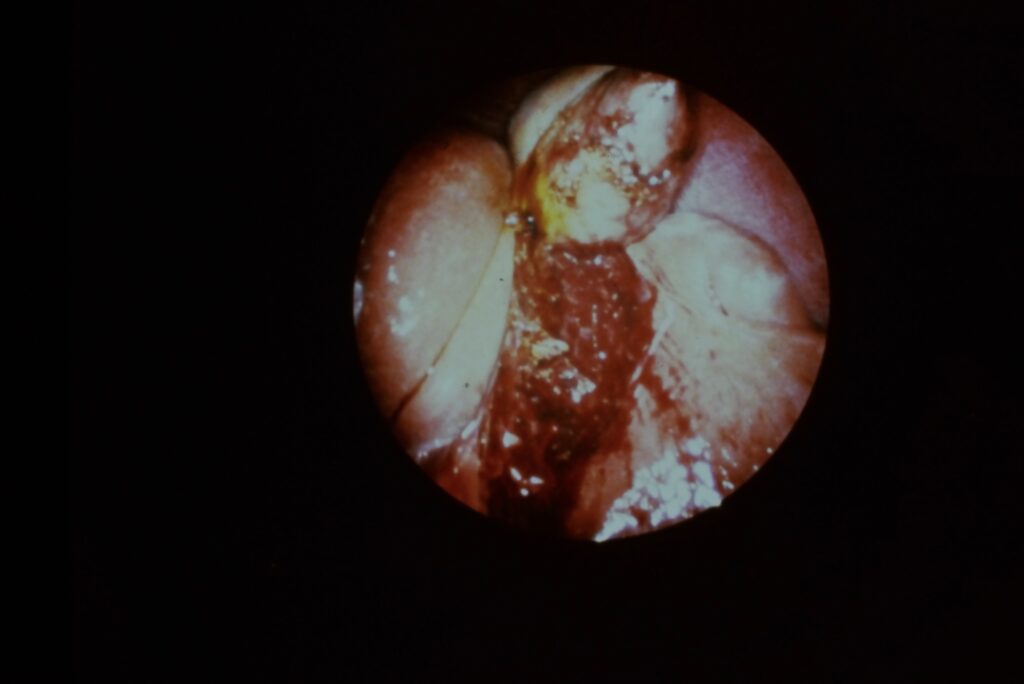

Circa 1991….early Laparoscopic surgery

scanner

This was the visualisation we achieved with our early laparoscopic Gallbladder surgery. Compare that with pic below.